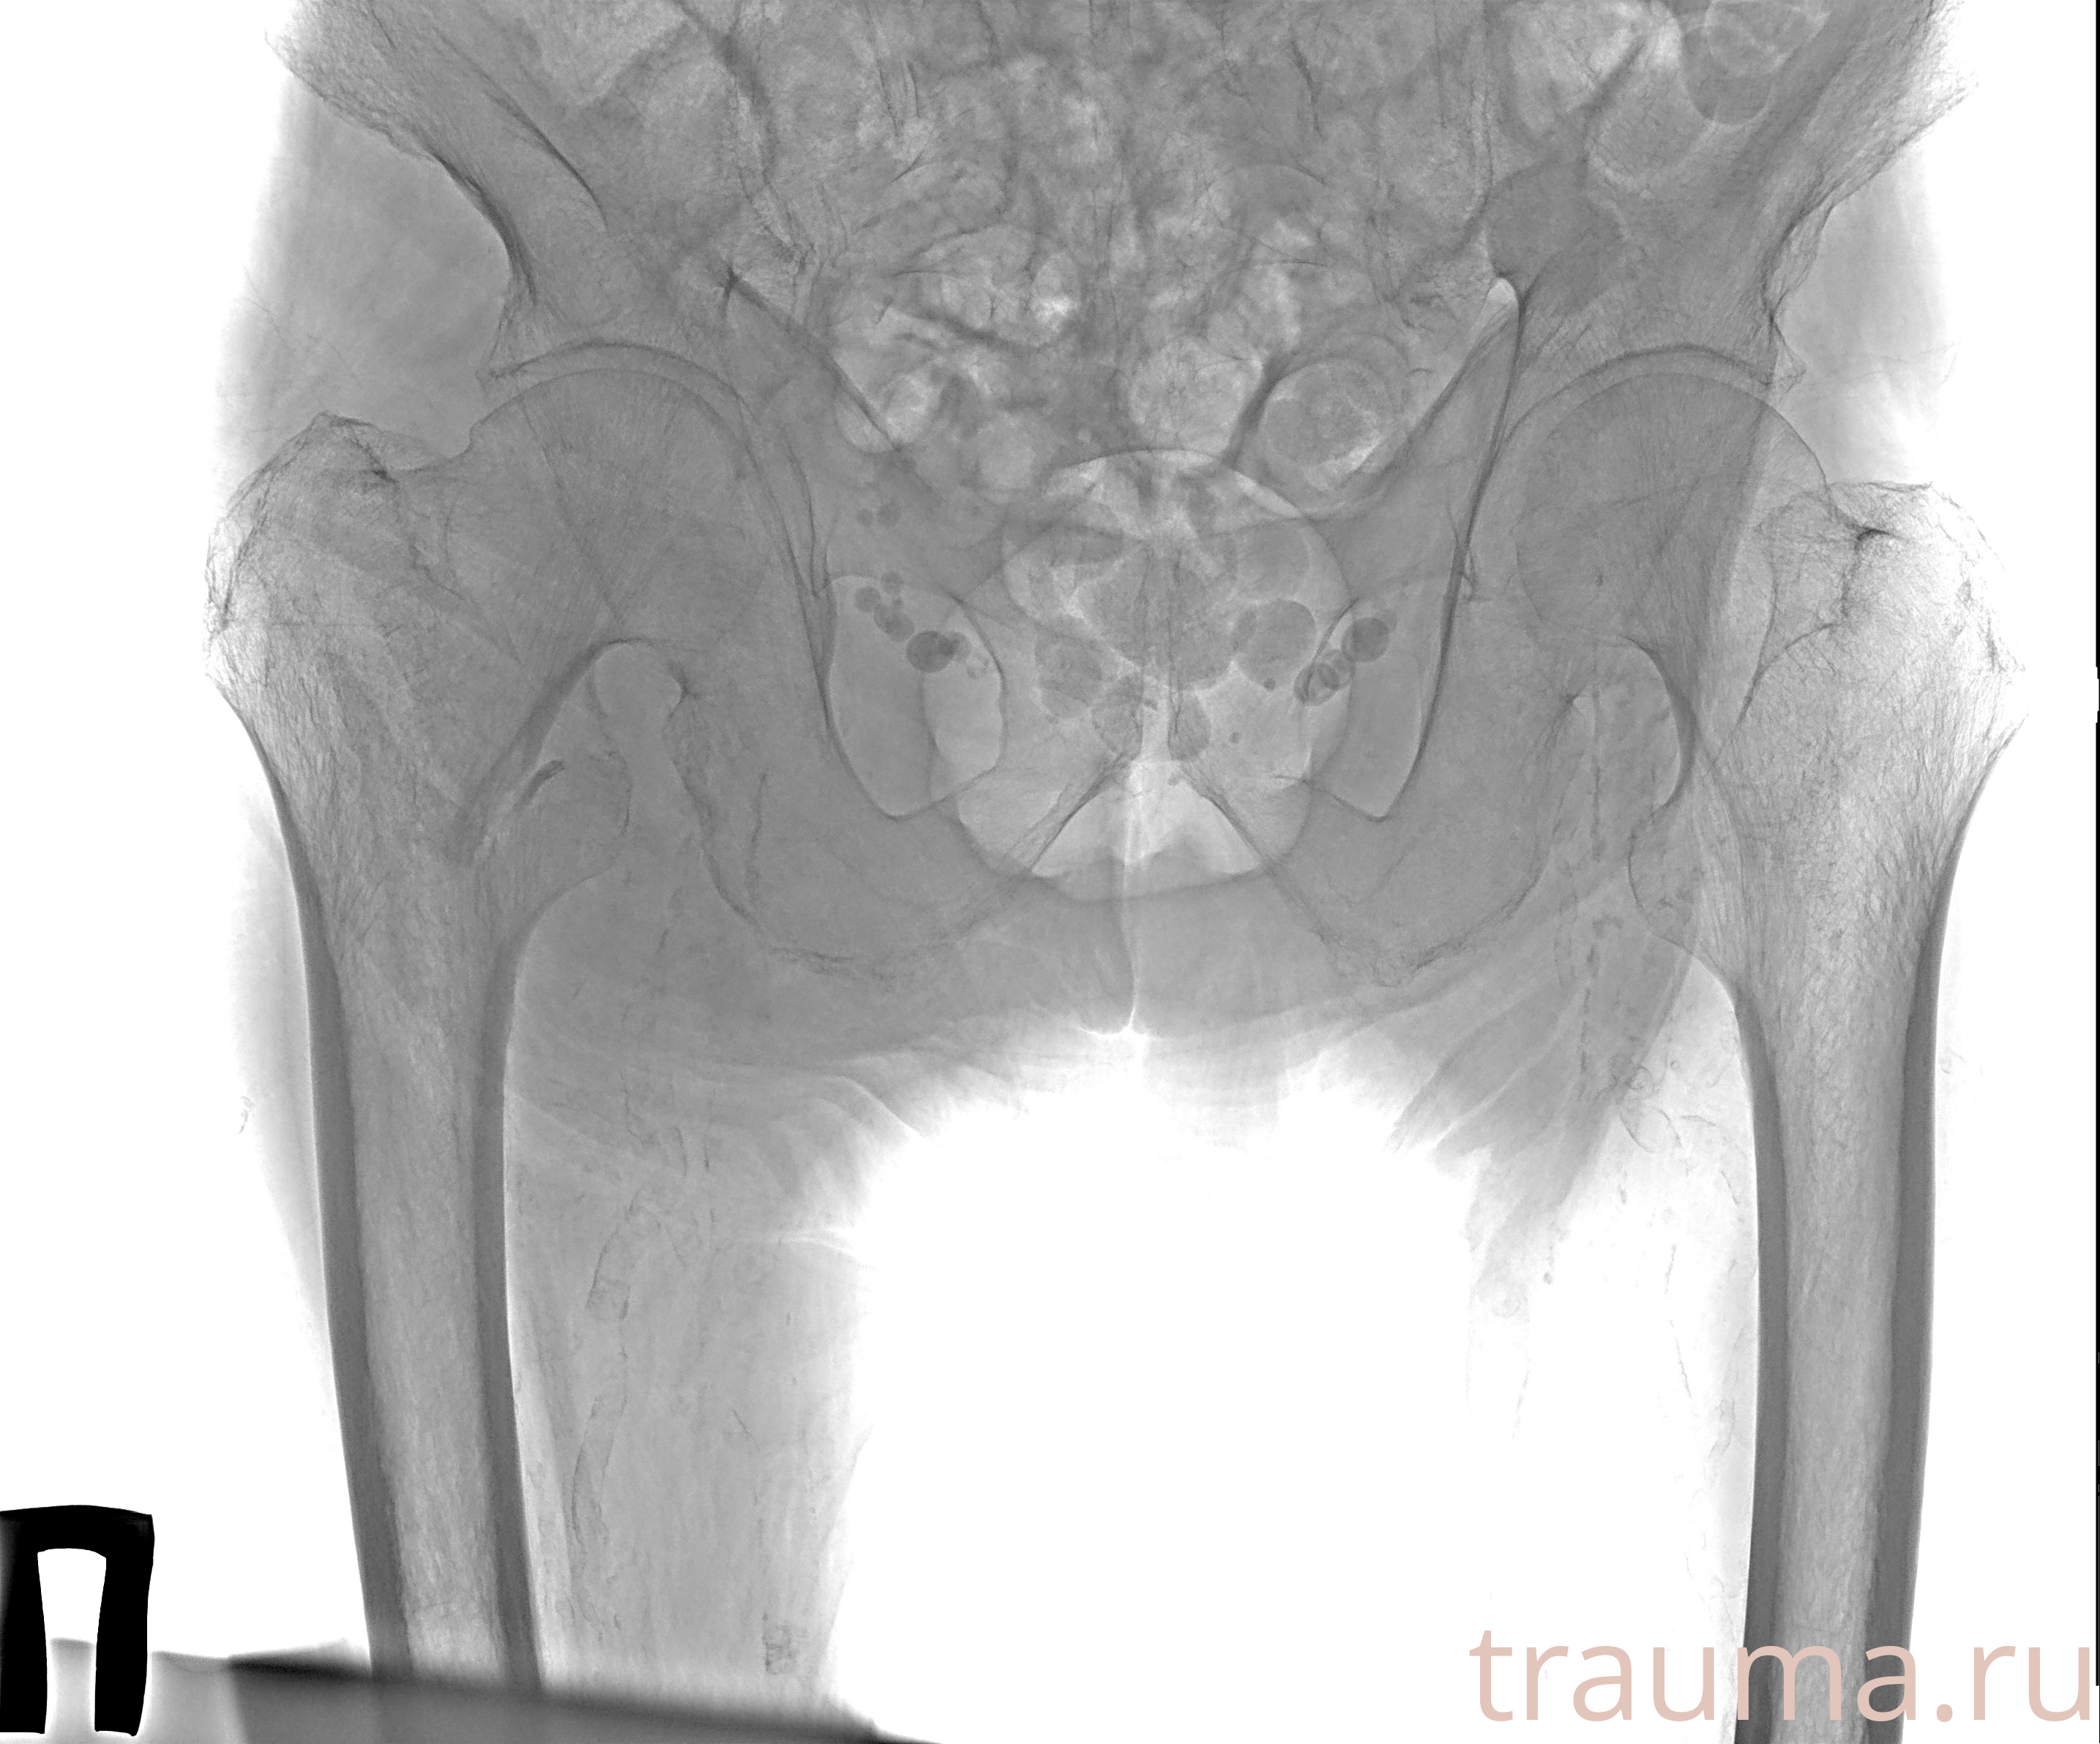

Рентген на дому: по вашему адресу приезжает врач-рентгенолог, травматолог-ортопед с мобильным рентгеновским аппаратом, проводит диагностику травмы или заболевания, делает необходимые рентгенограммы, дает рекомендации по дальнейшему лечению. Получить качественные снимки в домашних условиях возможно благодаря уникальной методике, разработанной МосРентген Центром для института  Склифосовского